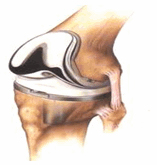

3. การผ่าตัดเปลี่ยนผิวข้อเข่าเทียมบางส่วน

การเปลี่ยนผิวข้อเฉพาะส่วน เป็นการเปลี่ยนผิวข้อเพียงซีกด้านในหรือซีกด้านนอกของข้อ ที่เป็นบริเวณรับน้ำหนักเข่าเท่านั้น และไม่มีการเปลี่ยนผิวของกระดูกสะบ้า รวมทั้งเส้นเอ็นไขว้ด้านหน้า ยังดีอยู่ สำหรับวัสดุที่ใช้ในการเปลี่ยนผิวข้อเข่าเทียมบางส่วนมีคุณสมบัติเช่นเดียวกับข้อเข่าเทียมชนิดทั้งข้อข้อเข่า

รูปภาพ การผ่าตัดเปลี่ยนผิวข้อเข่าเทียมบางส่วน